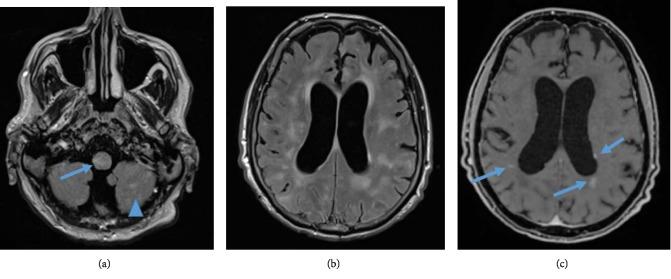

We present a case of a 54-year-old man with primary angiitis of the central nervous system (PACNS) who was initially admitted to a psychiatric clinic with a diagnosis of delirium. We discuss the difficulty in establishing the diagnosis of PACNS and provide the reader with some recommendations on how to promptly and correctly diagnose this disease in order to avoid potentially lethal outcomes.

我们报告一例54岁患有中枢神经系统原发性血管炎(PACNS)的男性病例,该患者最初因谵妄诊断被收治于精神科门诊。我们讨论了确立PACNS诊断的困难,并为读者提供一些关于如何迅速且正确诊断该病的建议,以避免潜在的致命后果。